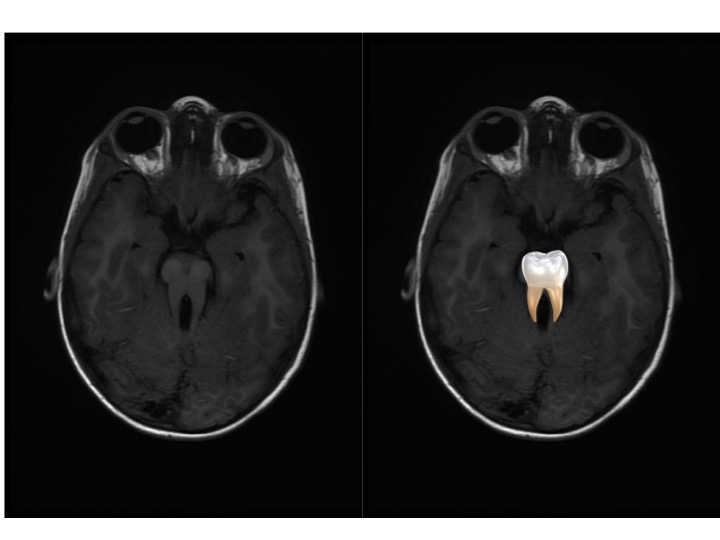

Molar Tooth sign in a patient with Joubert Syndrome Image

Molar tooth sign

appearance of the midbrain in an axial section in which the elongated superior cerebellar peduncles give the midbrain an appearance reminiscent of a molar or wisdom tooth.